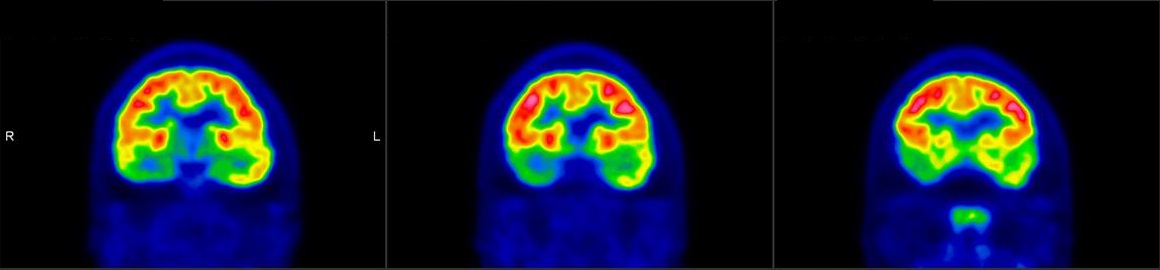

- Dementia

PET/CT scans with special tracers can show 3-dimensional images of blood flow and biomolecules deposition in the brain for diagnosis and monitoring the therapy progress of various neurological diseases, such as Alzheimer's, Dementia, Parkinson's disease, Huntingdon's chorea and autism. In 2018, the National Institute on Aging-Alzheimer's Association (NIA-AA) had revised the definition of Alzheimer's Disease (AD) from a syndrome diagnosed by a set of clinical criteria to a biological construct using abnormal protein deposits to define AD as a unique neurodegenerative disease that can lead to dementia. Our hospital has almost 20 years of experience in producing specific tracer to detect abnormal protein deposition in the brain.